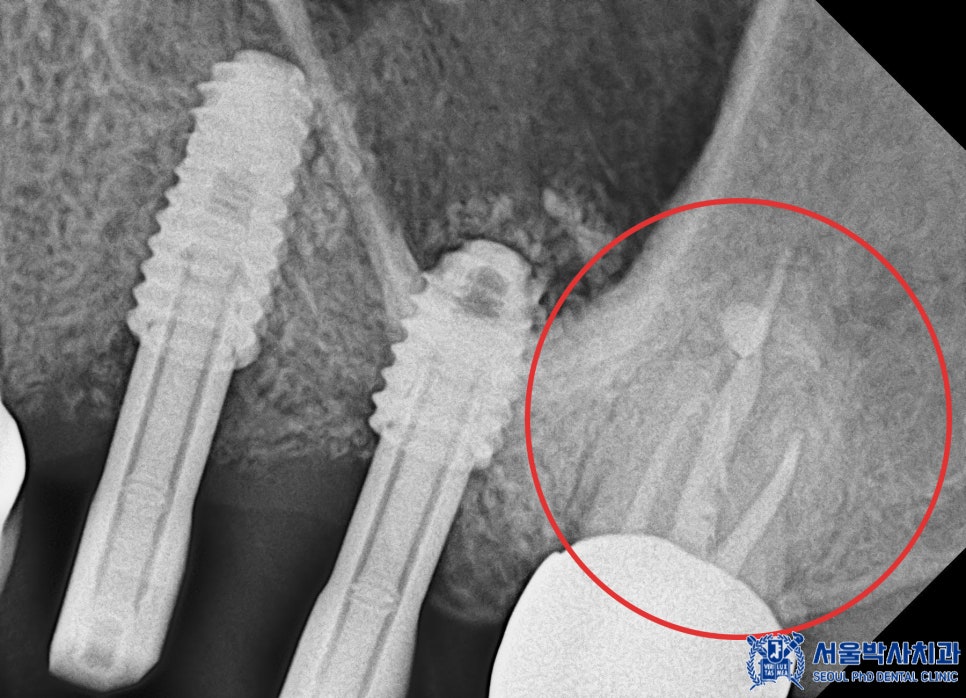

오른쪽 아래 기존 임플란트 중 뒤쪽 큰 어금니는

임플란트와 인공 치아를 연결해주는 부분이 파절되었고

앞쪽 큰 어금니 임플란트는 염증으로 인해

상태가 좋지 않았기 때문에

제거 후 재수술을 진행해야 했습니다.

이 과정에서 중요한 것은 임플란트가

정밀한 위치와 각도로 식립되는 것입니다.

임플란트의 식립각도는 수술 성공률과

직결되기 때문에 작은 오차도 결과에

큰 영향을 미칠 수 있습니다.